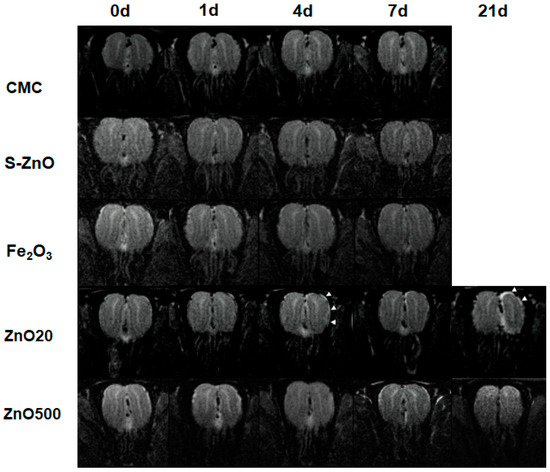

3.3. Structural Changes of the OE and OB